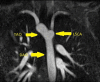

The Society for Cardiovascular Magnetic Resonance (SCMR) is an international society focused on the research, education, and clinical application of cardiovascular magnetic resonance (CMR). Case of the week is a case series hosted on the SCMR website ( https://www.scmr.org ) that demonstrates the utility and importance of CMR in the clinical diagnosis and management of cardiovascular disease. Each case consists of the clinical presentation and a discussion of the condition and the role of CMR in diagnosis and guiding clinical management. The cases are all instructive and helpful in the approach to patient management. We present a digital archive of the 2020 Case of the Week series of 11 cases as a means of further enhancing the education of those interested in CMR and as a means of more readily identifying these cases using a PubMed or similar search engine.